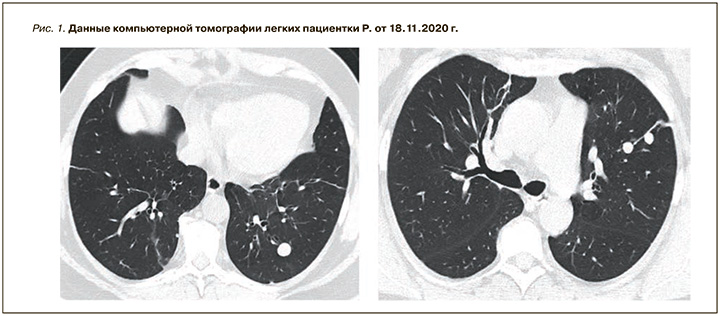

В ноябре 2020 г. при проведении КТ органов грудной клетки у пациентки были выявлены очаговые образования с четкими и ровными контурами (рис. 1). С целью верификации обнаруженных очаговых образований 29.01.2021 в Российском научном центре хирургии им. академика Б.В. Петровского больной была выполнена левосторонняя видеоассистированная торакальная полисегментарная резекция. Данные иммуногистохимического исследования от 15.02.2021: доброкачественная лейомиома? Динамическое исследование не проводилось, терапия не назначалась.